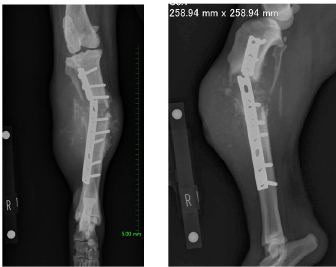

A 14-year-old spayed female Labrador retriever weighing 21.3 kg was referred to our hospital with a main complaint of chronic right-hind lameness. This patient had undergone surgery for right tibial fracture repair with implantation of bone plate and screws at a referral hospital 12 years ago. The patient showed no appetite, was not drinking, and was lethargic, with a body condition score of 1/5. The patient was unable to stand up on her own, her right hind limb was mostly weak, and she was unable to move independently using her left side. The patient’s state of consciousness was normal. On physical examination, her vital signs were normal (temperature: 38.1°C, pulse 104 beats/minutes with no heart murmur, respiratory rate with normal lung sounds: 32 beats/minutes). The mucous membrane showed a pale color because of severe anemia (packed cell volume 20.4%). In addition, the capillary refill time was delayed by <3 seconds, suggesting severe dehydration. The patient showed swelling and was warm to the touch from the right tibia to the femur, with a swollen right popliteal lymph node, which presented with a ruptured mass lesion approximately 7 × 10 cm in size. The thoracic radiograph was normal (Fig. 1). However, the right hind limb radiograph showed an osteolytic lesion accompanying the ruptured implant and loosening of the plate and screws, with surrounding soft tissue swelling (Fig. 2). Fine needle aspiration from this site suggested OSA (data not shown). Although we could not perform angiographic computed tomography because of the owner’s dissent, we performed amputation from the hip joint on the same day. Gross morphology showed severe inflammation surrounding soft tissues, the rupture of the stainless-steel bone plate, and we noted a non-medical band at the right tibia (Fig. 3). The patient was formally diagnosed with OSA after histopathological examinations (Fig. 4). After 24 hours hospitalization, we administered ampicillin potassium (20 mg/kg, BID) intravenously and prednisolone (0.5 mg/kg, SID) subcutaneously for postoperative care. Also, 24 hours continuous rate infusion of fentanyl (5 μg/kg/minutes) in lactated Ringer’s solution was used for analgesia. The patient was discharged to the owner the day after surgery for home care. The owner refused postoperative radiation therapy and chemotherapy. Unfortunately, this patient died 1 month after amputation.

Fig. 2. Limb radiographs. The right tibia showed an osteolytic lesion with rupture of orthopedic plate, loosening of screws, and also soft tissue swelling.